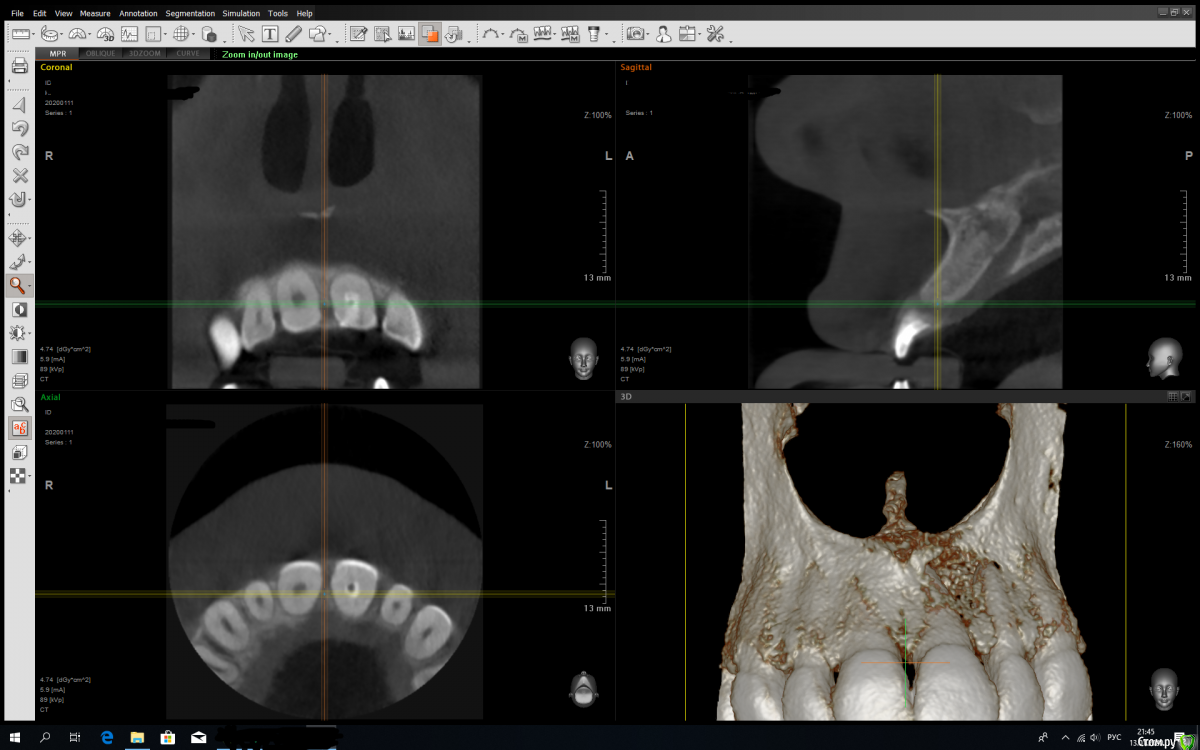

sst Опубликовано 13 января, 2020 Поделиться Опубликовано 13 января, 2020 (изменено) Добрый день!Диагноз кистаПосле КТ предложили удалять два зуба - сказали лечение уже не поможет.Хотелось бы услашать еще мнение(снимок КТ прилагаю)Спасибо! Изменено 13 января, 2020 пользователем sst Ссылка на комментарий

Jurai Опубликовано 14 января, 2020 Поделиться Опубликовано 14 января, 2020 срез КТ неинформативен. 1 Ссылка на комментарий